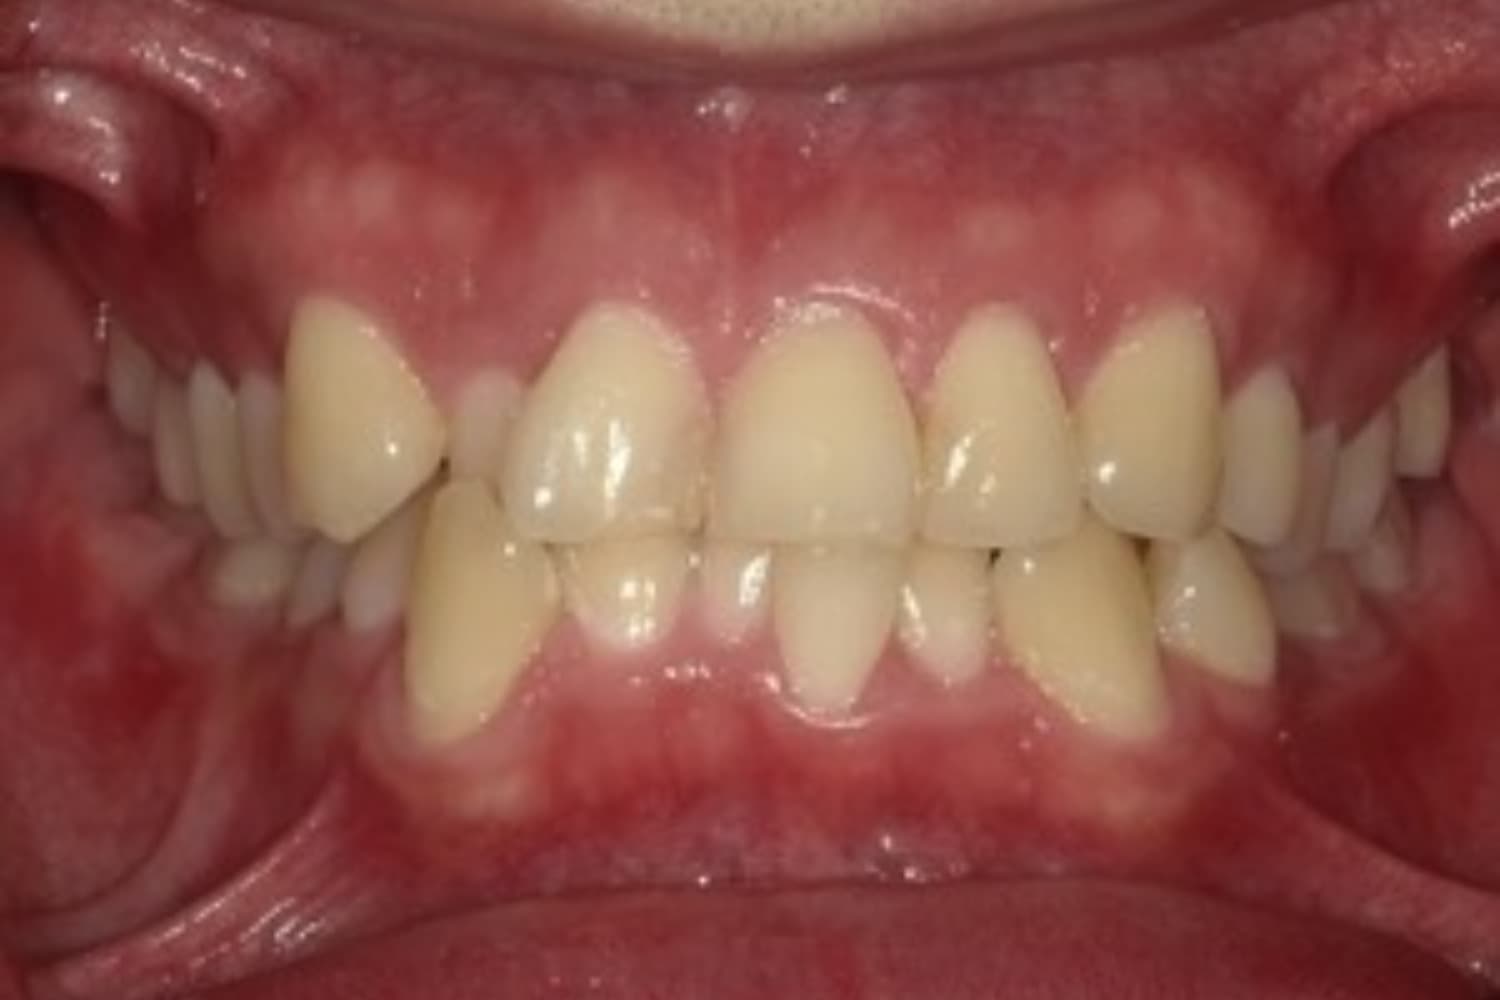

ガタガタとした歯並びや八重歯(1)

Before

After

ガタガタとした歯並びや八重歯をマウスピース矯正(インビザライン)にて治療

主訴

下の前歯のガタガタが気になる

治療期間

2年5カ月

費用

90万円

副作用・リスク

・矯正治療による歯の動きには個人差があり、想定より治療期間が延びることがあります。 ・矯正治療で歯を動かす際に痛みをともなうことがあります。 ・指示された通りに保定装置を装着しないと、歯並びや噛み合わせの後戻りを引き起こす可能性があります。